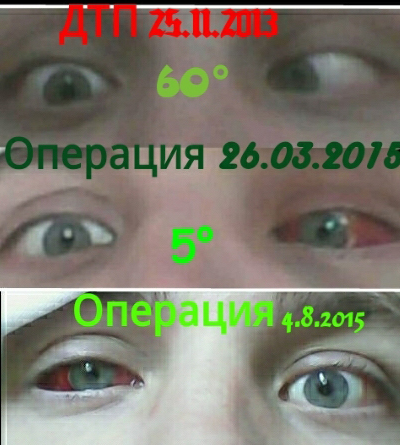

Диплопия: механизм развития и методы лечения

Раздел: Картинки жизни